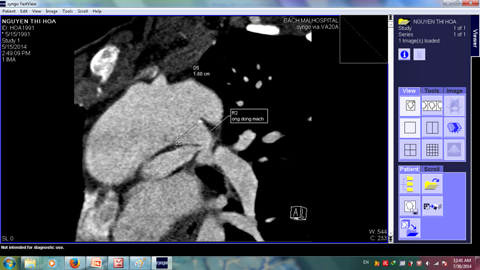

Sau đình chỉ thai, bệnh nhân đã được chụp MSCT hệ mạch phổi xem xét khả năng phẫu thuật sửa chữa toàn bộ. MSCT cho chẩn đoán PA-VSD, giãn nhẹ gốc động mạch chủ ( ĐK 45mm), động mạch phổi trái và phải có hội lưu chung, đường kính mỗi nhánh tương đối lớn ( 13 và 14 mm) , thân động mạch phổi rất ngắn, hẹp gốc động mạch phổi trái (Đk 5mm), không có tuần hoàn bàng hệ chủ phổi (MAPCAs), còn ống động mạch cấp máu cho hai phổi (Hình 2).

Hình 2: Hình ảnh chụp MSCT động mạch phổi cho thấy hai nhánh động mạch phổi phải và trái có hội lưu, hẹp gốc động mạch phổi trái (mũi tên trắng) và còn ống động mạch ( chú thích)